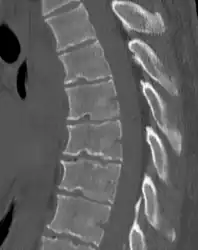

Scheuermann's disease on lateral CT of the T spine